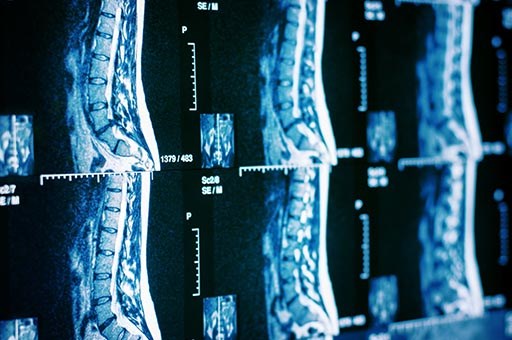

• Spinal Stenosis

Spinal Stenosis

Spinal stenosis is a condition characterized by the narrowing of the spinal canal, through which the spinal cord and nerve roots pass. This narrowing can lead to compression of neural structures, resulting in pain, muscle weakness, sensory disturbances, and, in advanced cases, difficulties with walking or even urinary and fecal incontinence.